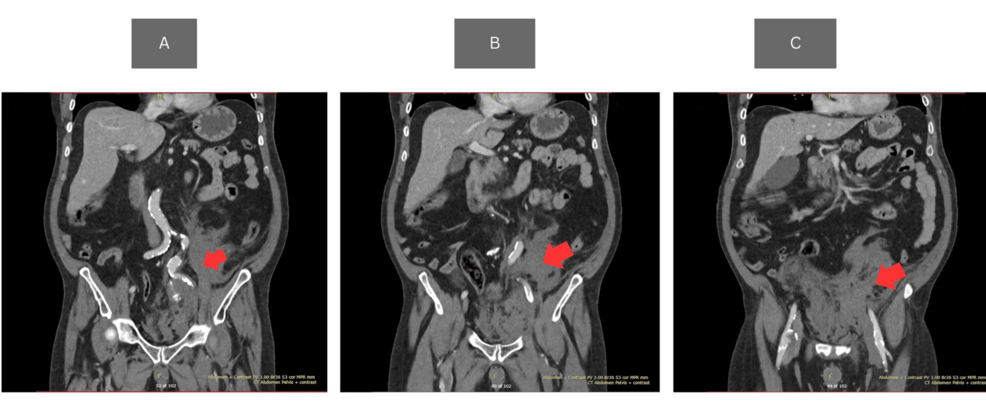

Ruptured Internal Iliac Artery Aneurysm Presenting as Syncope and Left-Sided Abdominal Pain: A Rare Cause of Collapse in the Emergency Department